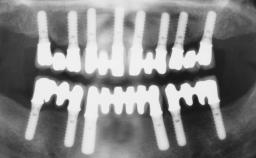

Immediate Loading of Four Implants in the Mandible and Final Restoration with a Full-Arch Metal Framework FDP

A fully edentulous 65-year-old woman was referred to our clinic for esthetic and functional dental rehabilitation. The patient presented with inadequate complete maxillary and mandibular prostheses, insufficient vertical dimension, and extensive tooth wear. The clinical examination and anamnesis showed no local or systemic contraindications, no signs or symptoms of bruxism, and an absence of smoking habits. The treatment proposed was implant placement in the mandibular interforaminal area and immediate loading with a fixed definitive prosthesis. A removable mucosa-supported complete prosthesis was indicated for the upper jaw, since its bone structure offered satisfactory retention and the financial condition of the patient disfavored a full-mouth implant-supported rehabilitation.

# of Implants 4

Type of Implants One-Piece

Prosthesis Type FDP

Loading Protocol Immediate